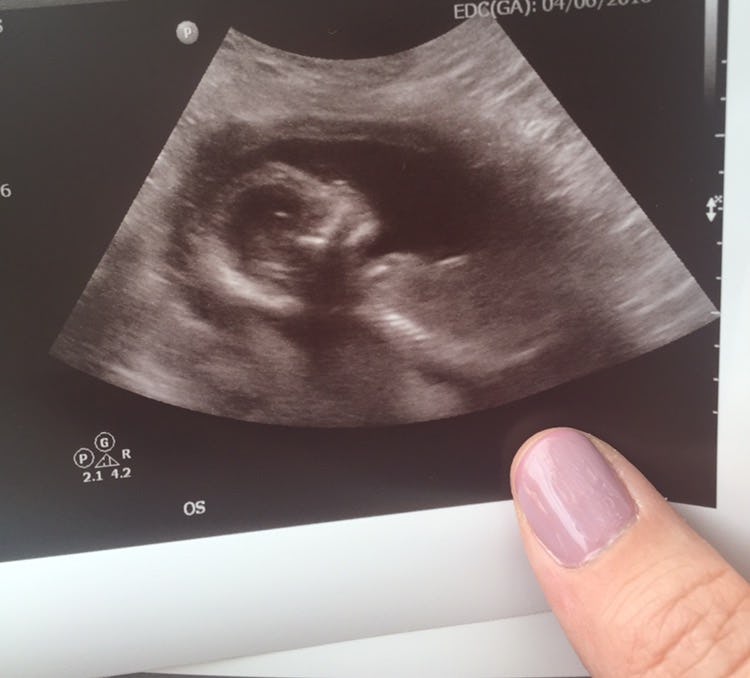

Much like how Trump knows nothing about what it's like to have an abortion, he knows even less about me and why I had one. Last year, after six months of trying to conceive, my husband and I were thrilled to find out I was pregnant. Even after taking advantage of all the advanced testing and screening that was available to me before the halfway mark of pregnancy, when we had my 20-week ultrasound, we discovered that my baby girl (whom we had already lovingly named Evelyn) had an extremely rare and lethal condition that was incompatible with life. Our baby had a very slim chance of making it to term, and if she did, she would live for a few hours at best, suffering the entire time.

Just over a week later, my husband and I made the heartbreaking choice to spare Evelyn a short life of pain by terminating my pregnancy. The choice wasn’t easy, but we knew that it was in the best interest of our child, and to us, that was the definition of being parents. Because I was past 20 weeks of gestation, I was counseled extensively on the way to end my pregnancy which was safest and most compassionate for both myself and my daughter. My termination took place over a three-day period in a well-known and respected hospital, with a kind and compassionate medical staff which treated me, my husband, and Evelyn with dignity.